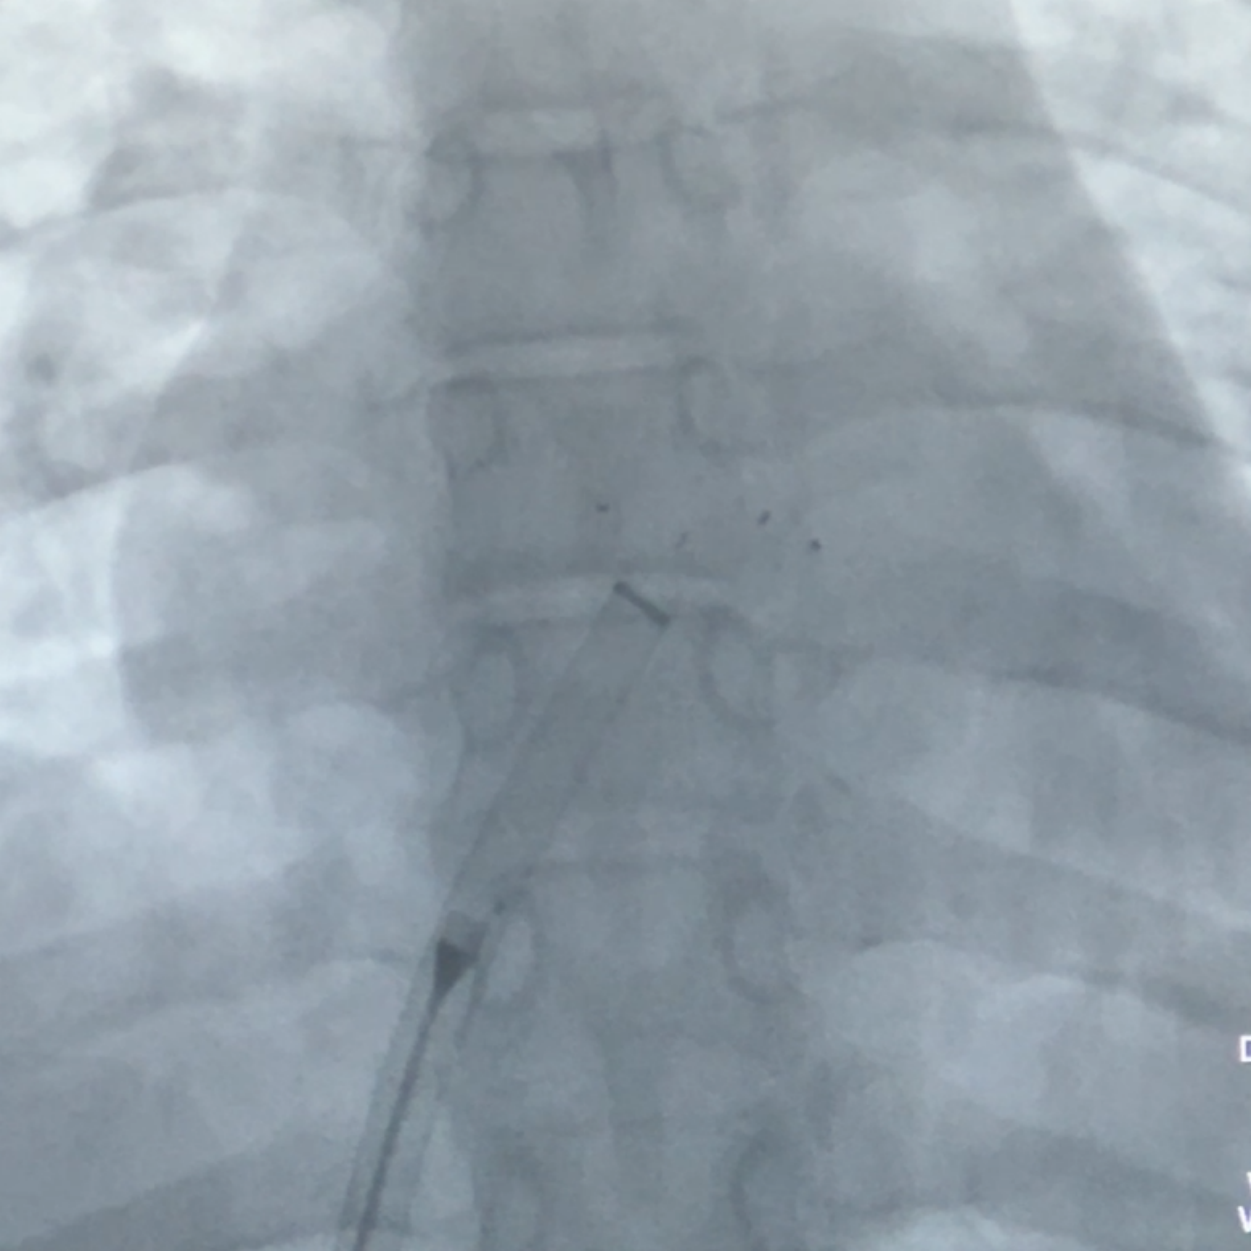

DSA下,左盘3个及腰部1个mark点推出,左盘展开,牵拉成型线,辅助左盘成型

后撤钢缆和鞘管,使左盘贴靠房间隔

右盘展开

固定钢缆不动 ,后撤鞘管展开右盘,钢缆及鞘管轻轻前推,使右盘贴靠于房间隔上

DSA下,封堵器5个mark点随着牵拉整体移动

前抵鞘管,逆时针旋拧钢缆,封堵器释放,DSA下,5个mark点相对位置不变